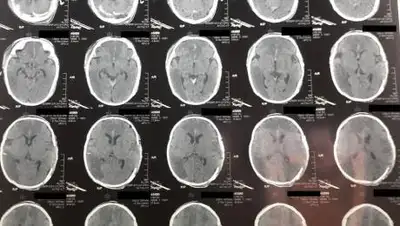

По информации lada.kz, 9 января ребенка с диагнозом "Острое нарушение мозгового кровообращения" (инсульт новорожденных) доставили в Мангистаускую областную многопрофильную детскую больницу.

У двухмесячного младенца зафиксировали отек головного мозга, дислокационный синдром и кому I-II степени.

10 января состояние ребенка удалось стабилизировать. В экстренном порядке ему провели операцию по трепанации черепа, которая продлилась два часа.